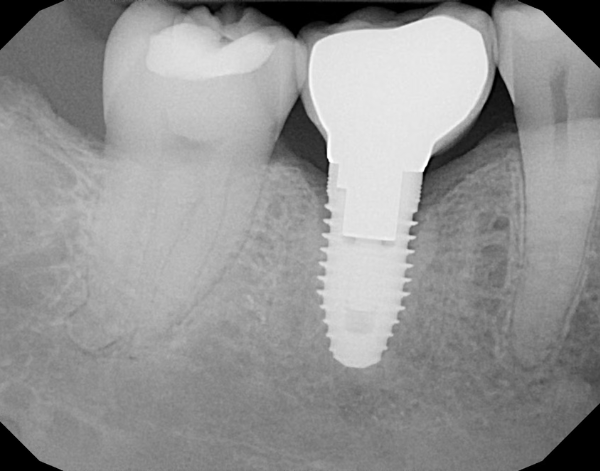

Image of a dental implant fitted by North Down Dental in Bangor, Northern Ireland.